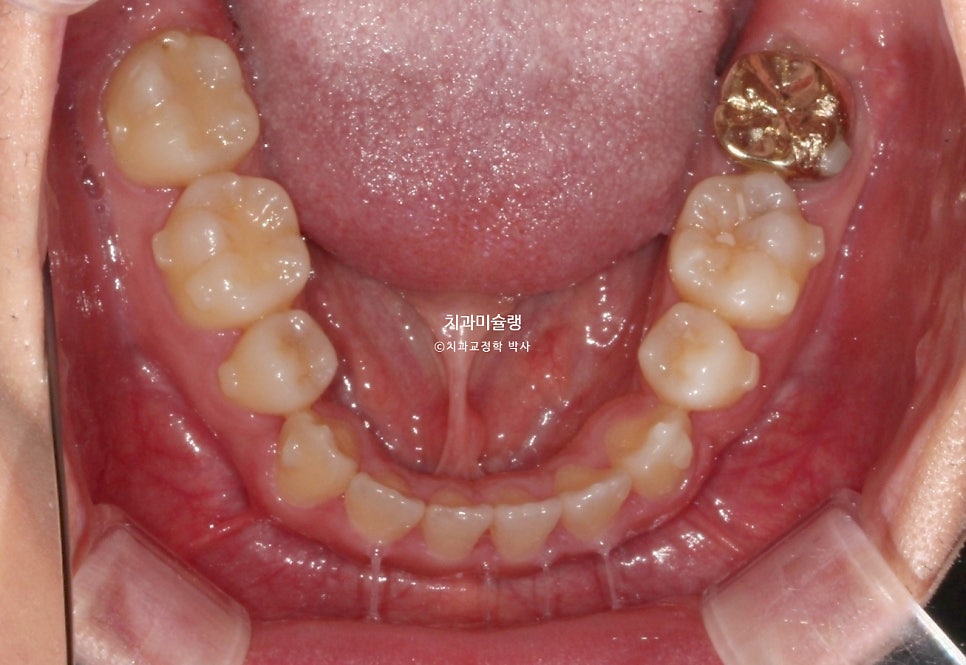

초진 시 구강 상태

2024년 봄 초진

2024년 봄 교정치료를 위해 내원한 환자분 입니다.

중심선 불일치, 반대교합, 덧니 등이 보입니다.

앞니가 뻗친 돌출 입니다.

그에비하면 어금니는 배열도 좋고 교합도 좋은 편이죠.

입이 잘 안다물어질 정도의 돌출입이며 웃을때 잇몸이 과하게 보이는 거미스마일도 있습니다.

입 다무는게 편치 않아서 턱끝에 자갈턱 또는 호두턱이 생길 정도의 돌출입 이라면 작은어금니 4개 발치교정이 필요합니다.

병원에 자주 못오는 환자분의 사정을 고려하여 인비절라인 교정 권유드렸습니다.